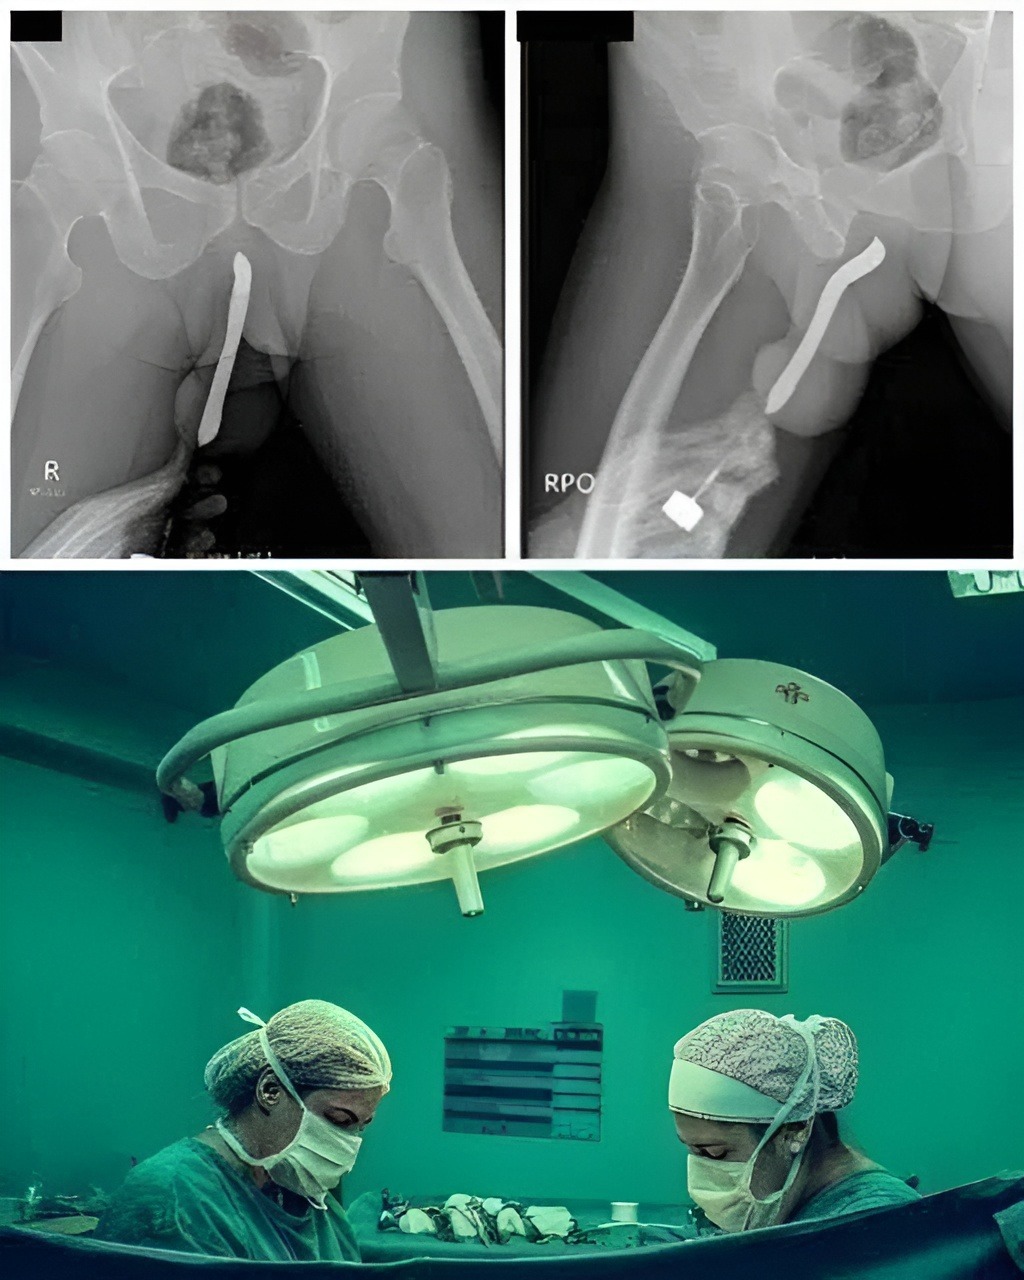

The X-ray That Explained Everything

Once she arrived at the emergency room, doctors began running tests. Because the cause of her pain was unclear, they ordered a scan to rule out internal bleeding or abdominal complications. What they found instead was the household tool lodged deeper inside her body than she realized — not due to intentional usage, but due to the angle, force, and the completely accidental way it had slipped.

The medical team immediately prepared for a controlled procedure to remove the object safely, as improper handling could worsen the injury. Fortunately, they were able to retrieve it without major surgical intervention, and there were no long-term complications.